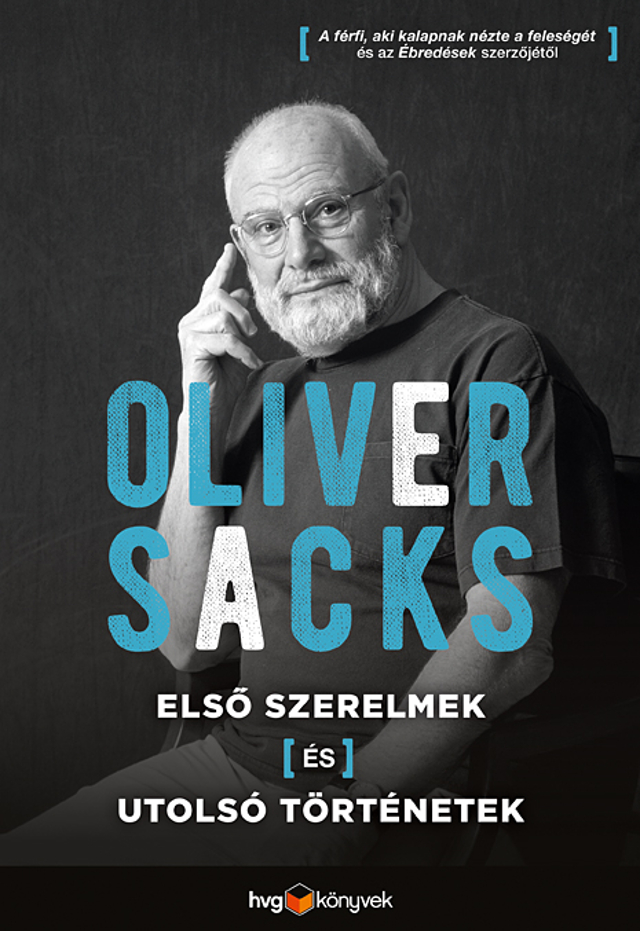

A fenti cikk Oliver Sacks Első szerelmek és utolsó történetek című könyvének szerkesztett részlete.

Oliver Sacksot neurológiai esetleírásaiért és az emberi viselkedés legkevésbé ismert megnyilvánulásai iránti szenvedélyes érdeklődése tette közkedveltté. Utolsó esszékötete egy személyesebb hangvételű elmélkedés. A könyvet itt rendelheti meg kedvezménnyel.